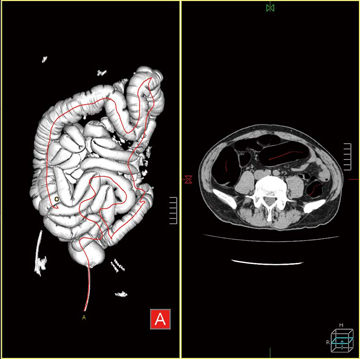

解析する画像データの読み込みを行うと,腹部の空気領域が自動的に抽出され三次元画像として表示される。大腸部分には,観察経路となる芯線が設定される(図4)。芯線領域抽出ボタンを押すことで,小腸など観察に不必要な部分が取り除かれ,大腸部分のみを表示させることができるため大腸の走行や狭窄部位の有無などの観察が容易となる(図5)。

図4 芯線設定画面 |

図5 芯線抽出画像 |